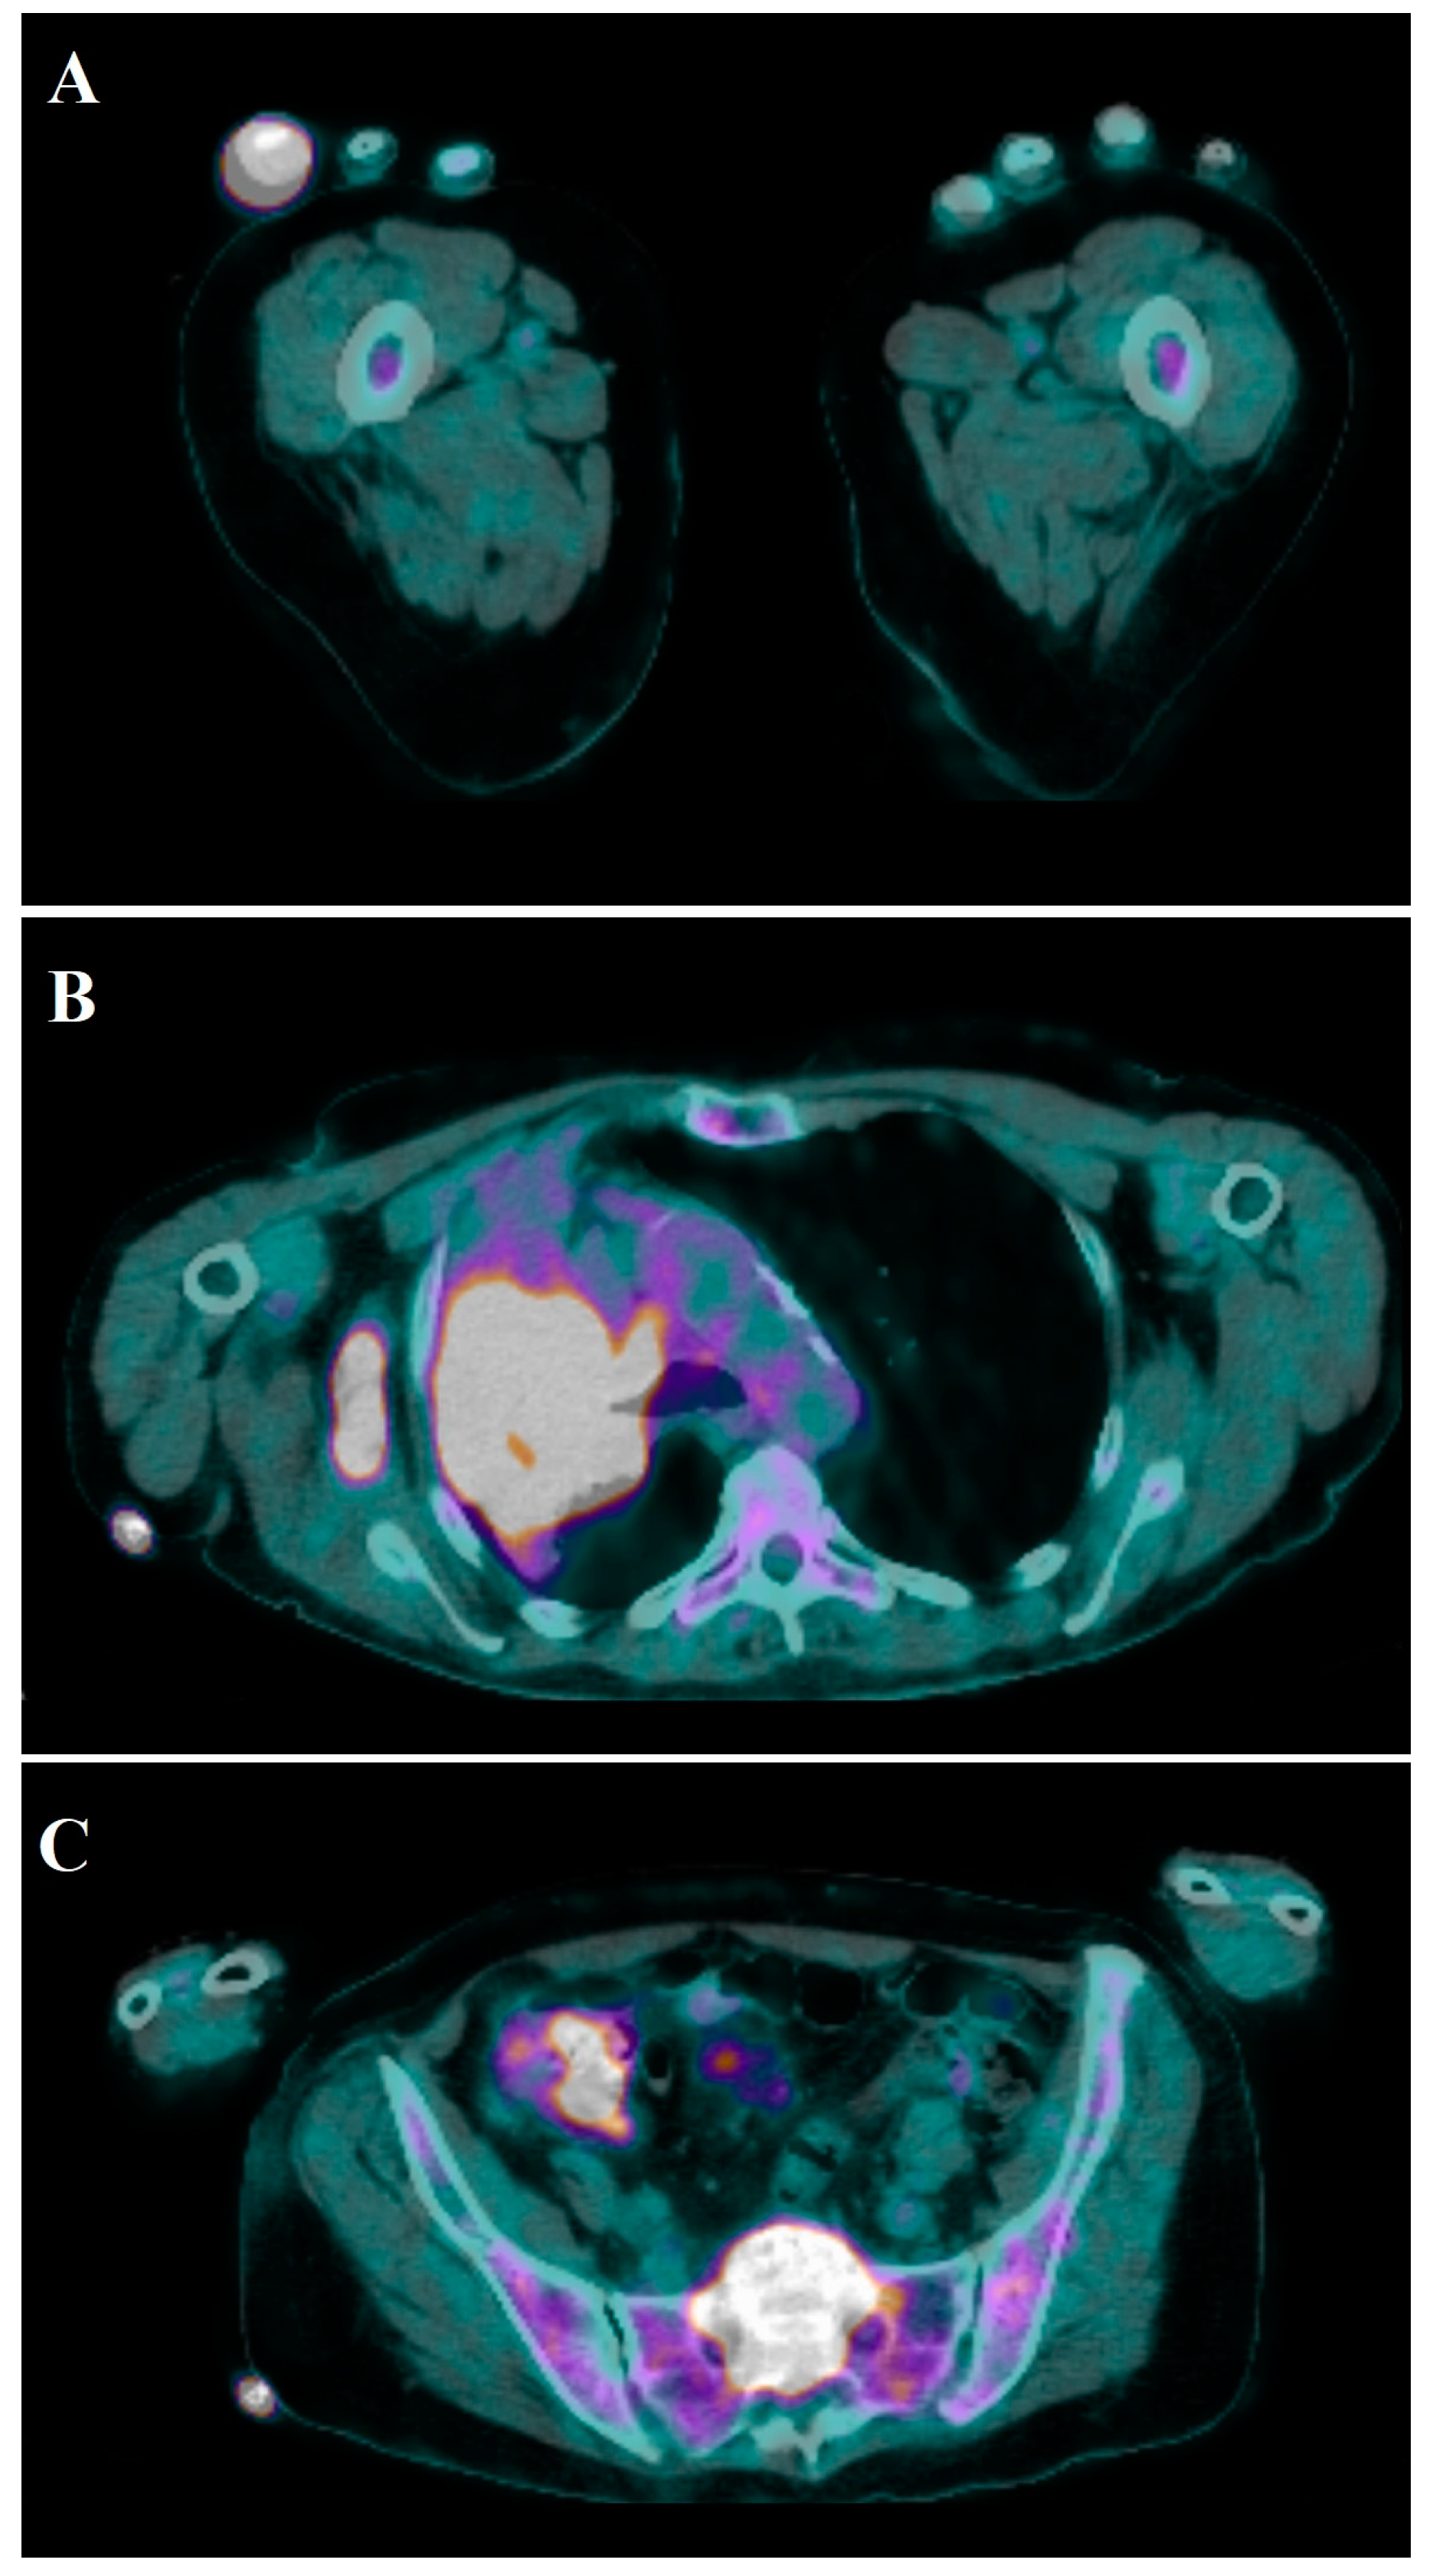

4.2. Imaging